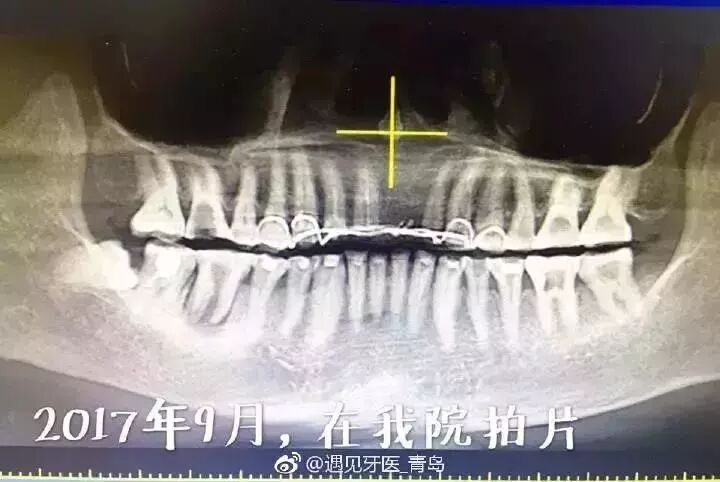

女孩不到三十岁,被建议拔除10多颗牙!第一波90后已经开始掉

女孩不到三十岁,被建议拔除10多颗牙!第一波90后已经开始掉牙了…